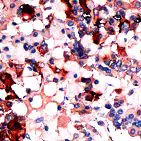

染色定位

细胞质

tsh